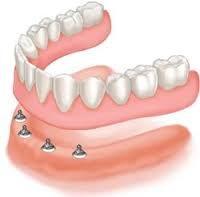

รากฟันเทียมขนาดเล็ก ผลิตจากวัสดุไทเทเนียมที่ออกแบบมาเพื่อเลียนแบบรูปร่างของรากฟันจริง ใช้พิเศษสำหรับรองรับฟันปลอมแบบถอดได้ โดยจะใส่ลงไปบริเวณสันเหงือกฟันบนด้านหน้าประมาณ 2 ตัว และฟันล่างด้านหน้าประมาณ 2 ตัว โดยออกแบบฟันปลอมให้มีตัวยึดสำหรับlockพิเศษกับรากฟันเทียมนี้